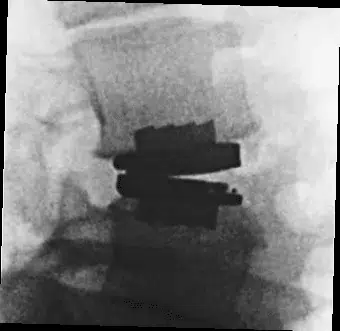

The prodisc L Anterior Lumbar Total Disc Replacement is a motion-preserving surgical procedure used to treat damaged lumbar discs that cause chronic lower back pain. It involves removing the affected disc through a small anterior (front) incision and replacing it with the prodisc L implant, an FDA-approved artificial disc designed to maintain natural spinal movement. This approach can relieve pain while avoiding the stiffness commonly associated with spinal fusion in appropriately selected patients.

prodisc L Gallery

Click to enlarge image